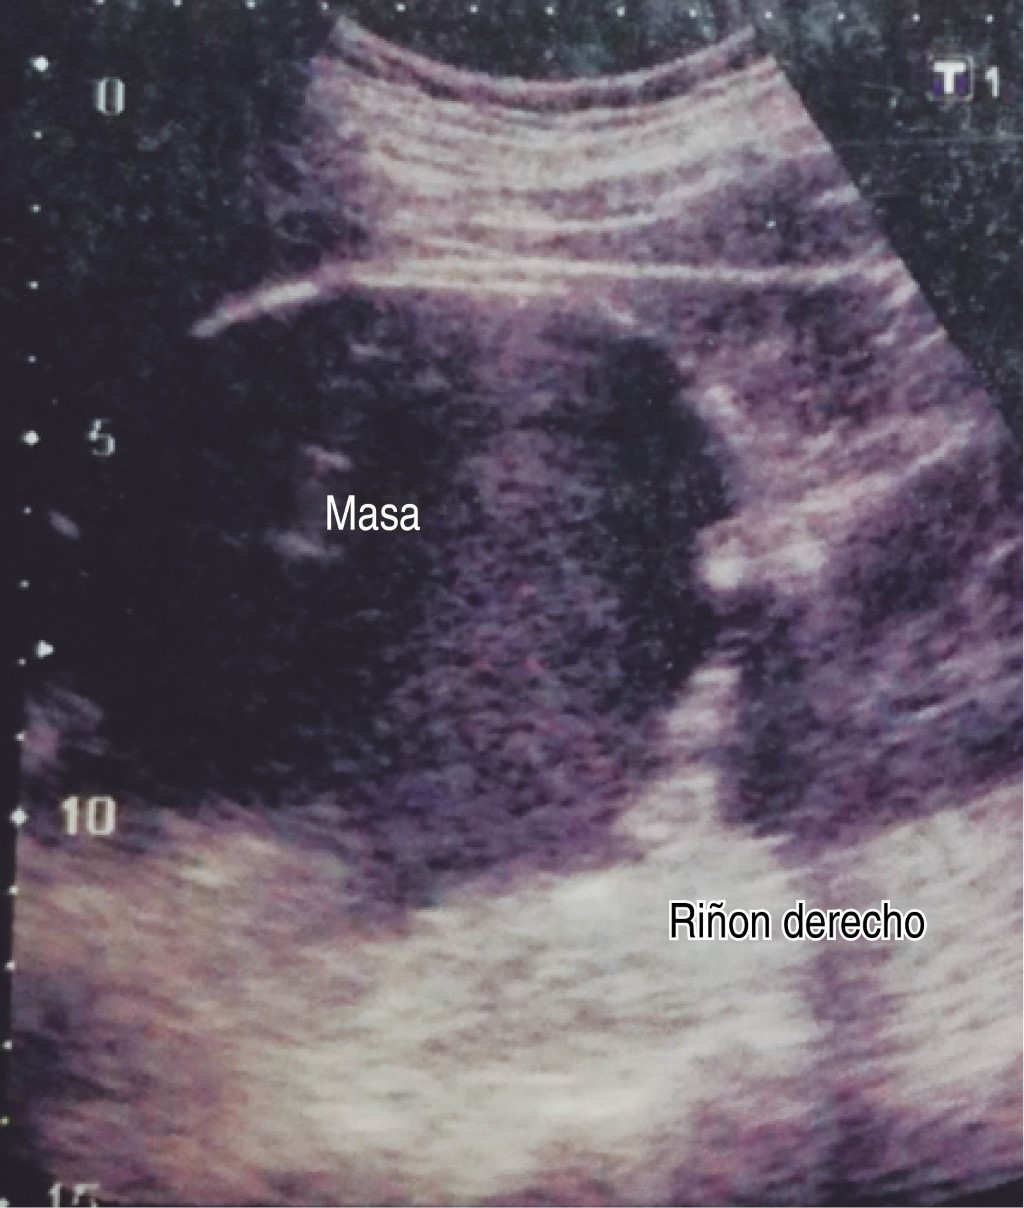

Ultrasonido de marzo reporta hígado de tamaño, forma y situación normales con borde inferior derecho irregular, de ecogenicidad heterogénea por presencia de una masa anecoica de forma redondeada y con bordes bien delimitados, paredes delgadas; sugestivo de quiste simple (Figuras 1 y 2).

Figura 2